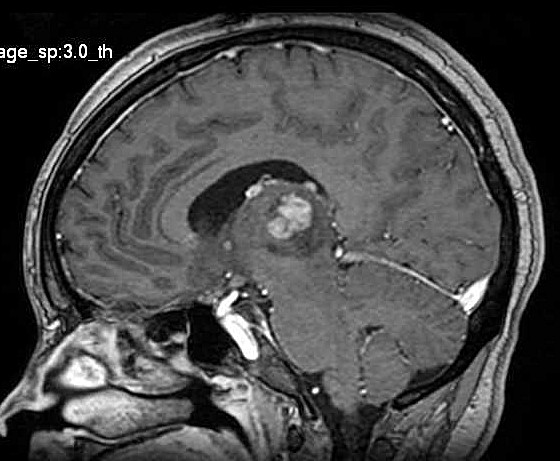

| Fem. 17a. |

| Nódulo sólido homogêneo preenchendo o III ventrículo, com limites precisos, com hipossinal em T1 e hipersinal em T2 e FLAIR, que se impregna por contraste paramagnético. Lesão menor implantada no assoalho do IV ventrículo provavelmente representa disseminação por via liquórica. |

| F. 17a. Tumor teratóide rabdóide atípico de III ventrículo. RM | HE | VIM, GFAP | HHF35, desmina, 1A4 | AE1AE3, EMA |